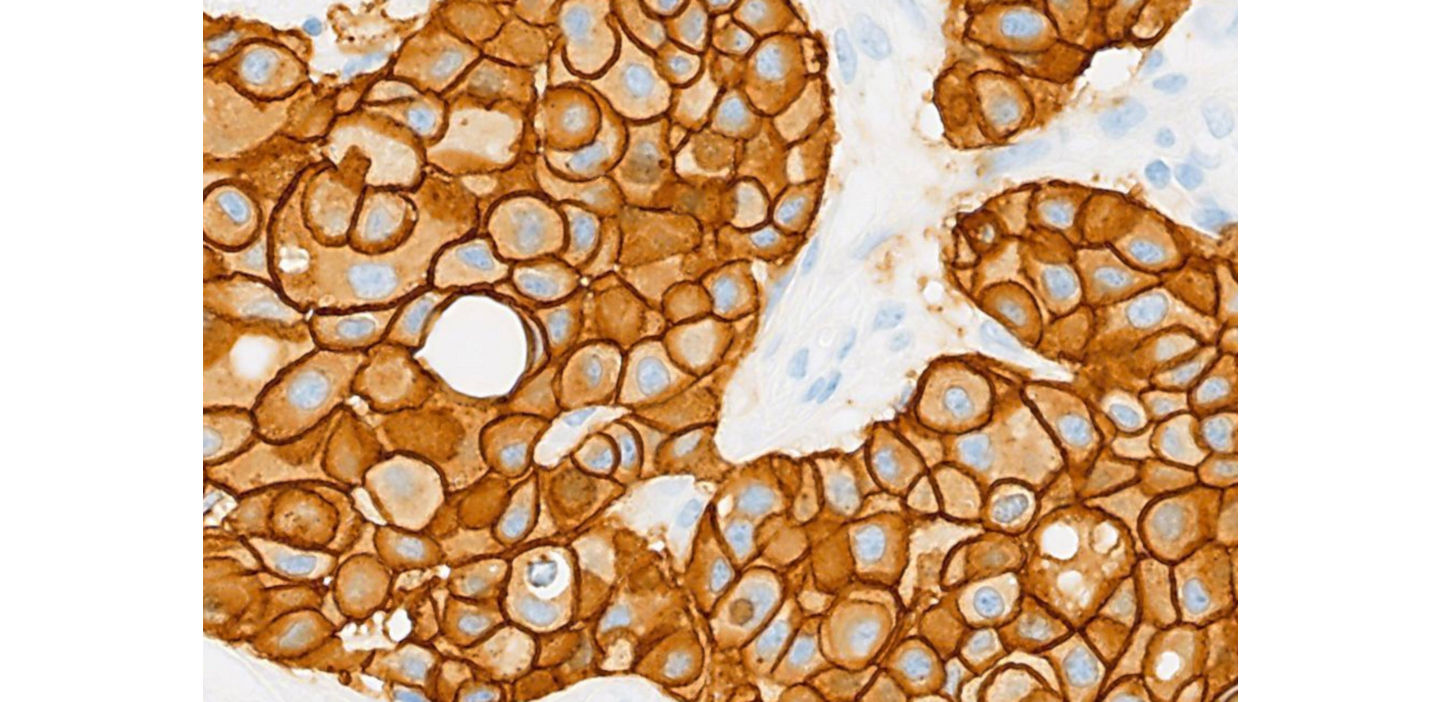

Five reasons why our HER2 (4B5) assay continues to be the trusted diagnostic assay of choice

Roche’s portfolio of immunohistochemistry (IHC) and in situ hybridization (ISH) breast cancer diagnostic assays provide high sensitivity, specificity and consistency. We continue to innovate to broaden clinical utility of these assays to include new indications – and support clinicians in making decisions that lead to better care for more patients.

Here are five reasons why the Roche HER2 (4B5) assay1 remains the trusted IHC predictive assay of choice for laboratories and clinicians alike.